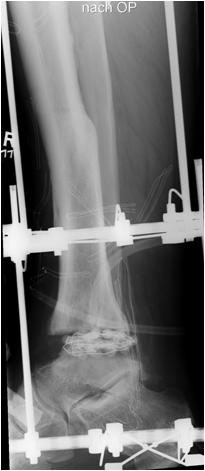

• Primäre oder posttraumatische Arthrose des OSG und USG (Abbildung 1, Abbildung 2).

• Revision einer gescheiterten Fusion des OSG/ USG (Abbildung 3, Abbildung 4).

• Pseudarthrosen (Abbildung 5, Abbildung 6).